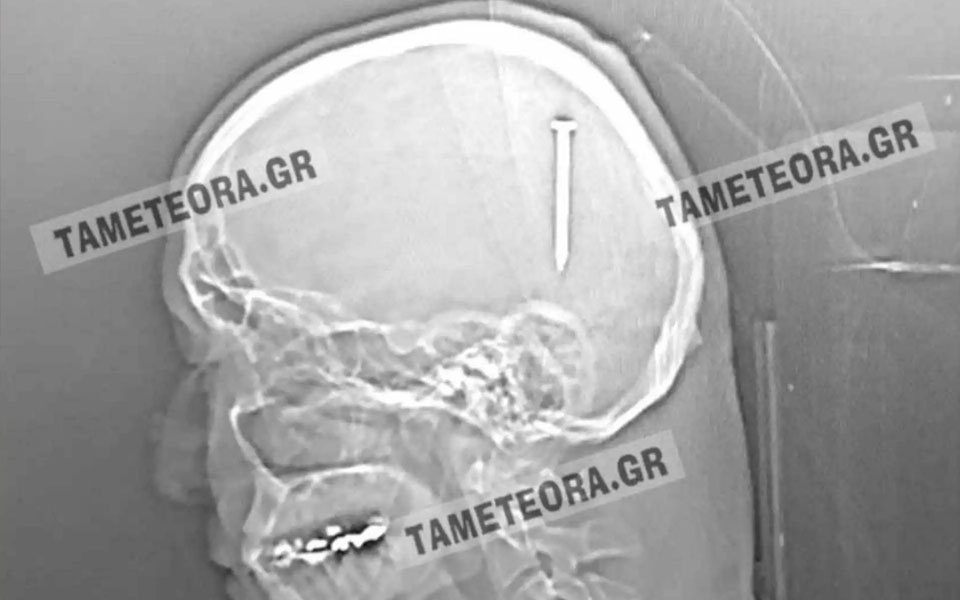

«Άγιο» είχε ένας άνδρας στη Καλαμπάκα, ο οποίος βρέθηκε ξαφνικά με ένα καρφί πέντε εκατοστών στο κεφάλι του.

Όλα συνέβησαν όταν ο πρωταγωνιστής της ιστορίας, κατά τη διάρκεια εργασιών, ένιωσε ένα τράνταγμα, χωρίς όμως πόνο ή κάποιο άλλο σύμπτωμα.

Αρχικά μεταφέρθηκε στο Κέντρο Υγείας Καλαμπάκας και στη συνέχεια στο Γενικό Νοσοκομείο Τρικάλων. Από εκεί «πήρε τον δρόμο» για το Πανεπιστημιακό Νοσοκομείο Λάρισας, όπου του έγινε επέμβαση και του αφαιρέθηκε το καρφί με επιτυχία.

Σύμφωνα με την ιστοσελίδα tameteora.gr, ο Καλαμπακιώτης αναρρώνει υπό παρακολούθηση, αλλά εκτιμάται ότι δεν διατρέχει κανέναν κίνδυνο η υγεία του. Πρόκειται πραγματικά για ένα σπανιότατο περιστατικό, καθώς αν το καρφί βρισκόταν ελάχιστα χιλιοστά από το σημείο που σφηνώθηκε, θα ήταν πολύ επικίνδυνο για την υγεία του τραυματία.